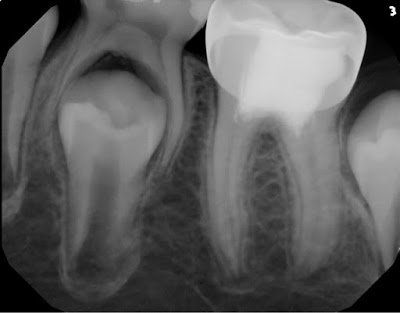

3 year recall finds tooth a symptomatic and functional. Root development is complete and appears normal.

While previous apexigenesis procedure have been used to keep the pulp alive in order to complete root development, these new materials seem to give a better prognosis and are an exciting advance in the development of vital pulp therapies.